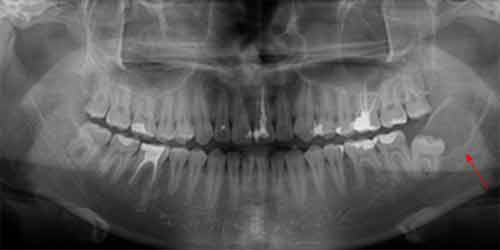

智齒造成囊腫

2008年4月拍攝

2011年6月拍攝